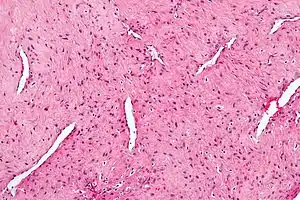

| Micrograph of a nasopharyngeal angiofibroma H&E stain. | |